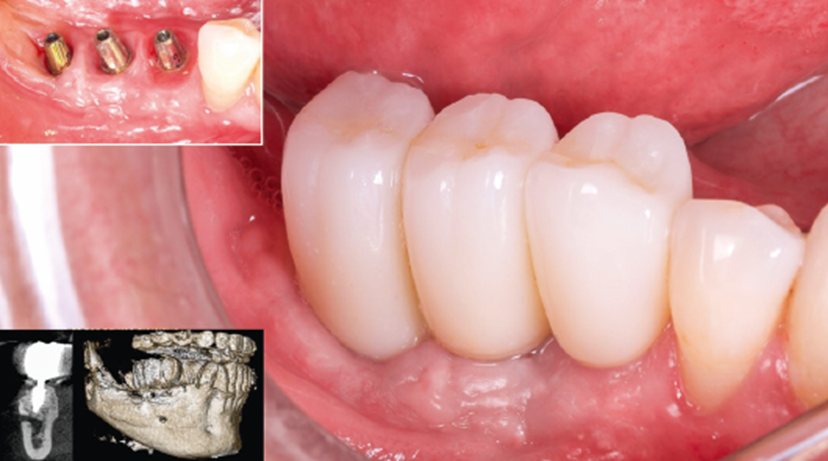

Após três meses, constatou-se a neoformação óssea adequada.Assim, foram instalados três implantes cone-morse Maestro (Implacil Osstem) com estabilidade primária satisfatória e aproximadamente 20 Ncm de torque de inserção (Figura 8). Após a instalação dos implantes, para ganho de volume tecidual e diminuição da remodelação do tecido ósseo, foi realizada a colocação de enxerto ósseo xenógeno com colágeno (Extra Graft, Implacil Osstem / Figura 9). Três meses após a osseointegração, os implantes foram reabertos para instalação dos pilares protéticos (Ideale, Implacil Osstem) e confecção das coroas provisórias, seguidas da finalização com as cerâmicas definitivas unitárias em zircônia monolítica após mais três meses de terapia (Figuras 9 e 10).